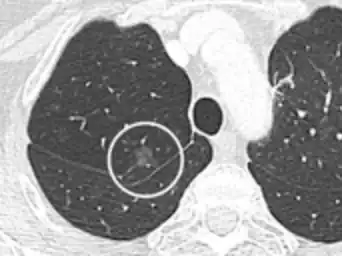

Thin slice and maximal intensity projection of a lung nodule, the latter better visualizing vascular convergence.[9]

• Vascular convergence is where vessels converge to a nodule without adjoining or contacting the edge of the nodule, and is mainly seen in peripheral subsolid lung cancers.[9] It reflects angiogenesis.[9]